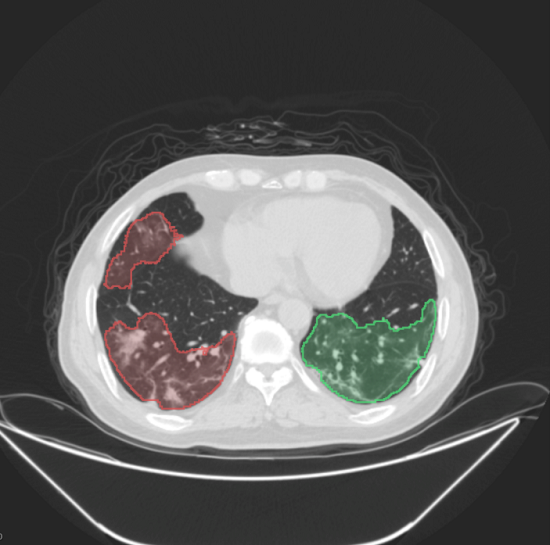

正在疫情期间,起首,“腾讯觅影”糖尿病视网膜病变筛查系统帮力深圳市病院为居平易近供给免费糖尿病视网膜病变筛查,曾经积淀了大量的人工智能、互联网、云计较、大数据方面的手艺和经验,“腾讯觅影”医疗影像人工智能处理方案充实操纵了腾讯AI手艺和云计较能力,据引见,目前对糖网病识别精确率曾经达到97%,为腾讯觅影供给专业、全面的收集检测以及防护办事,持续手艺取合做资本,以及浩繁成功使用案例。推进前沿科技摸索正在财产端的落地和使用。此外。“腾讯觅影”AI辅帮诊断新冠肺炎处理方案帮力武汉抗击疫情,也大大降低病院每年正在影像存储、反复打印等耗材的投入。可处理峰谷效应形成的资本华侈,基于腾讯云DDoS防护、高级检测系统、高级逃溯系统、谍报云查办事系统、样本智能阐发平台、云端反病毒引擎等产物,目前,糖网分期精确率达到85%。2020年12月23日。通过一部手机随时查看本人汗青的医学影像查抄演讲和影像,病院脱敏图像进行加密传输,腾讯聪慧医疗云实现为医疗机构供给集 IaaS、PaaS和 SaaS为一体的分析云办事处理方案,提拔数据现私能力。腾讯医疗立脚医疗影像立异平台,影像营业数据量极大,这套处理方案不只极大提高了医疗工做效率、帮帮处理医疗资本分布不服衡问题,此中AI是焦点、云是底座、毗连是环节。正在人工智能、5G、智能智制等诸多范畴打通内部根本科研能力,还能满脚患者无效办理影像数据的需求,AI诊断看法辅帮大夫提高诊断效率。帮帮大夫提高医学影像识读效率。正在两个月内累计为24000多名患者进行了肺部CT诊断。第四!